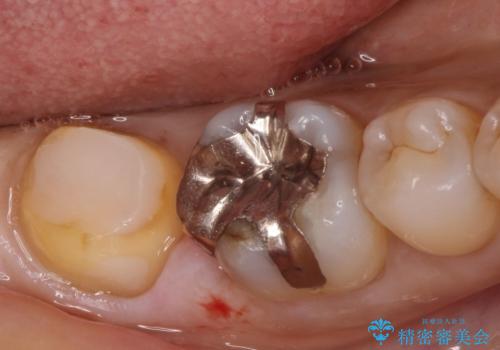

唾液から歯を守るため、ラバーダムシートを装着し古い材料を全て除去したうえで、う蝕を取り治療しました。

レントゲン写真から古い詰め物が神経と近接している事がわかります。万一に備え、ラバーダムシートを装着しながら治療を行いました。(万が一、虫歯の除去中に神経が露出した場合、神経を唾液から守るため。)

その後、新しい土台を立て、仮歯に置き換えたのち、フルジルコニアクラウンにて治療を行いました。